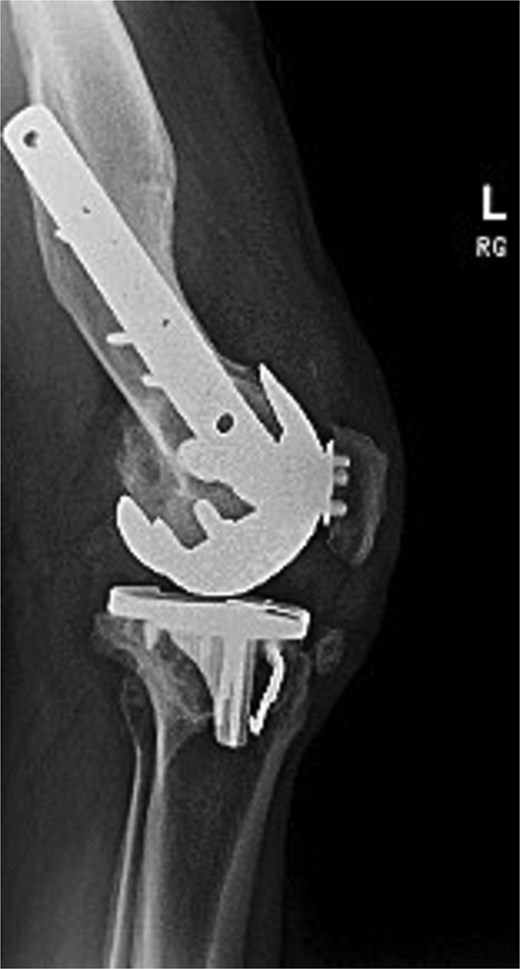

Figures 3 and 4 show a postoperative lateral and AP radiograph of the left knee. The patient was able to fully extend his knee after surgery and instructed to weight bear as tolerated until his two-week follow-up. Patient-reported outcome measures were completed at 2 year follow up (Table 1) with no reported complaints or issues at that time.

Postoperative lateral radiograph of the left knee 1 year after robotic-assisted TKA with hardware retention. The new femoral and tibial components are in place. The retained femoral plate and screws sit flush against the lateral cortex.